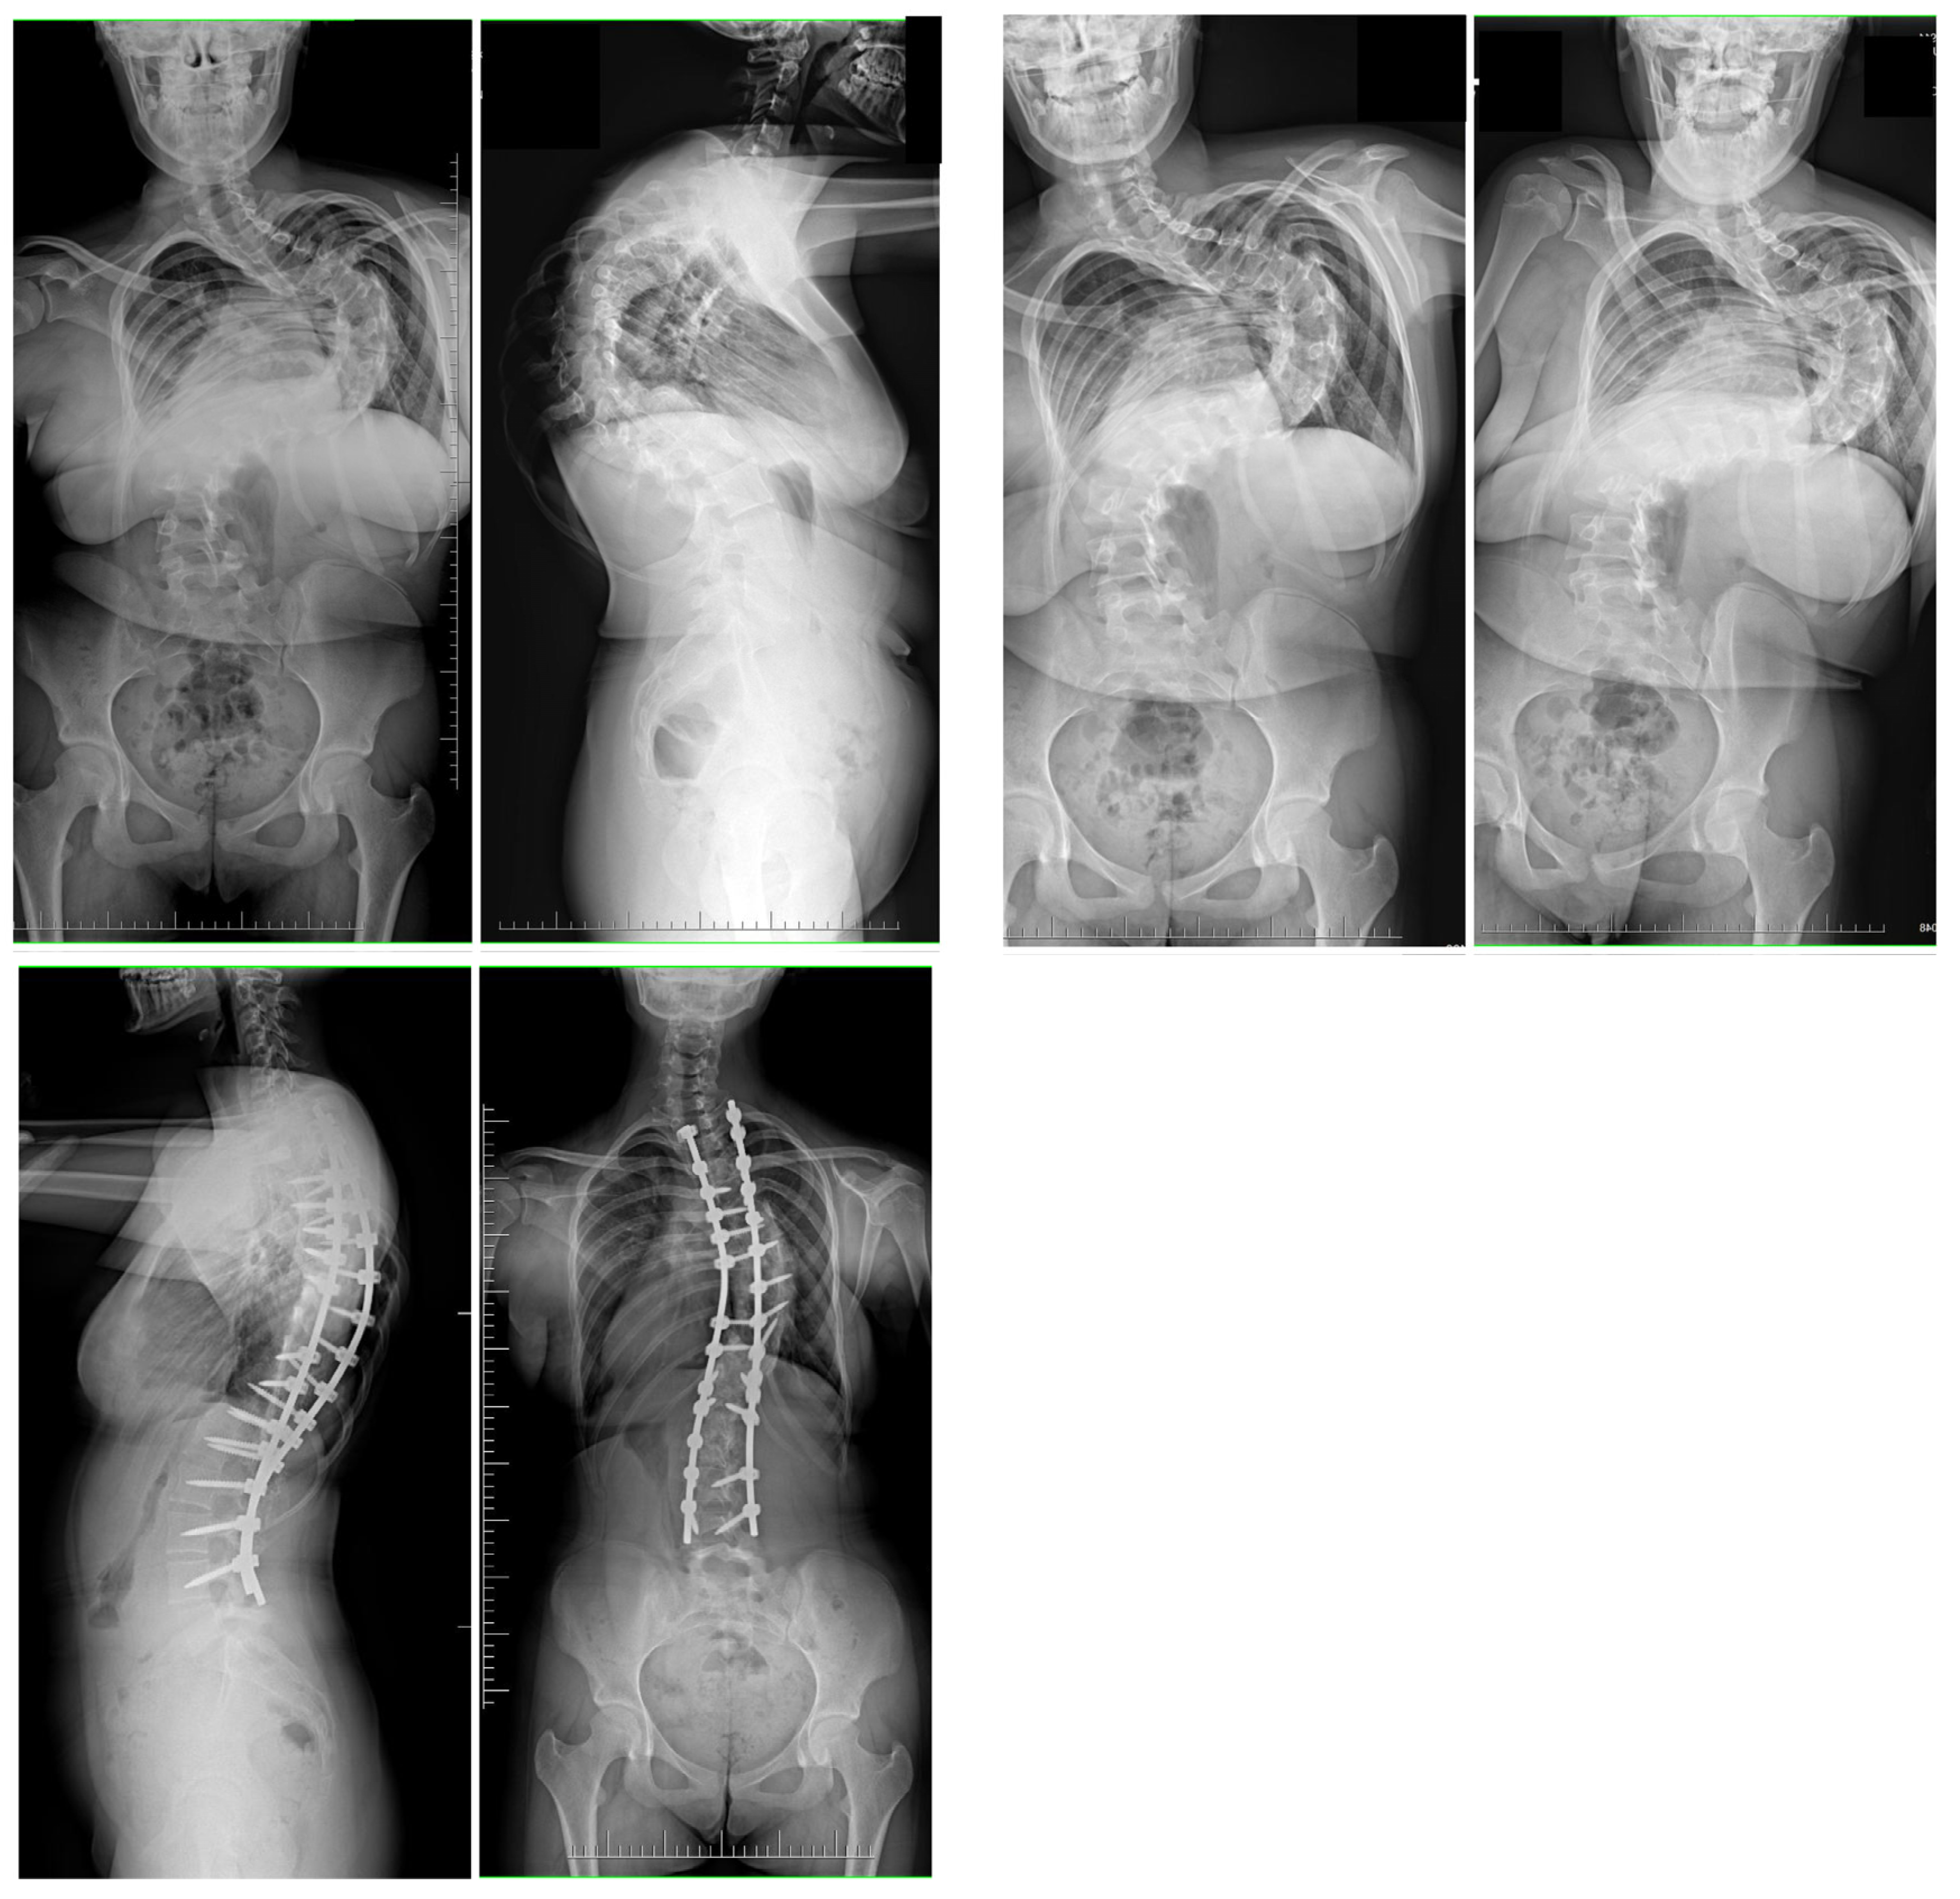

2.3. Surgical Technique

3.1. Clinical Characteristics and Radiographic Outcomes